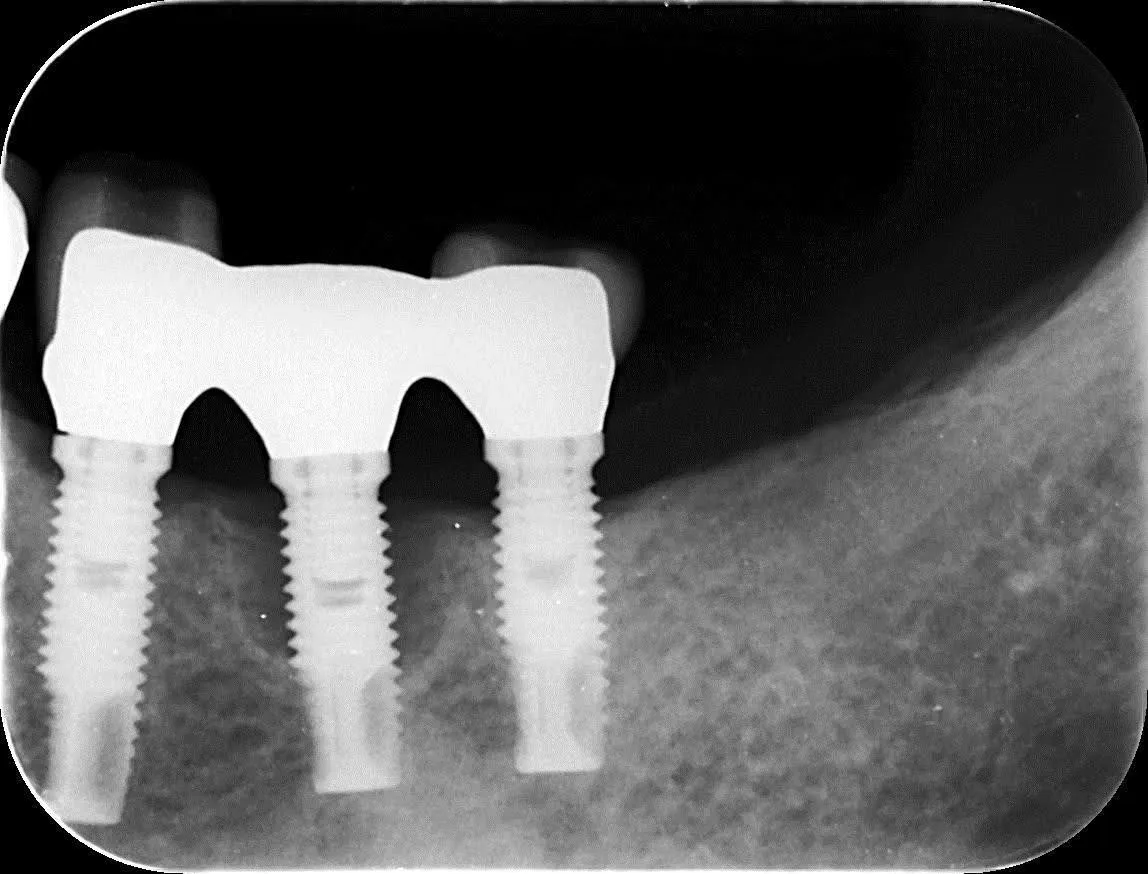

―過去に他院で埋入したインプラントのフォローアップ

炎症を起こして真ん中のインプラント周囲の骨がかなり溶けています。

冠も適合が悪く隙間ができています。

- 治療費(税込): 40万

- 治療期間: 6ヶ月

- 治療回数: 8回

- 副作用(デメリット): 保険が使えない

外科処置で骨の再生を促し、土台と冠を作り直しました。

真ん中のインプラント周囲の骨が見事に再生しています。

当院では、過去に治療した後の不具合も対応しています。遠慮なくご相談ください。